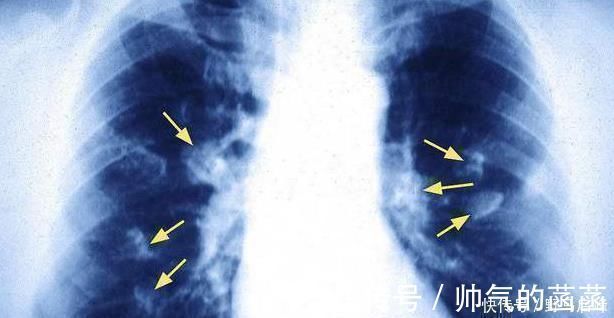

【 吸烟|肺癌一发现都是晚期错早期往往有蛛丝马迹,是身体在向你求救】据我们所知,癌症的治疗能力不是很高,但是与中后期患者相比较。如果癌症早期发现线索,能够采取适当的措施和积极的治疗,癌症状况仍然得到良好的控制,甚至有些人已经扭转了癌症。现在很多朋友都没有定期体检的习惯,这也很容易错过早期发现癌症的一部分。对于得癌症的肺癌,任何人都不太陌生。肺癌也在初期消失了。你身体出现这四种症状的时候,可能是肺癌在路上的信号,不行!

■肺癌来临前,身体也是蜘蛛网痕迹,注意到这四种身体表达!